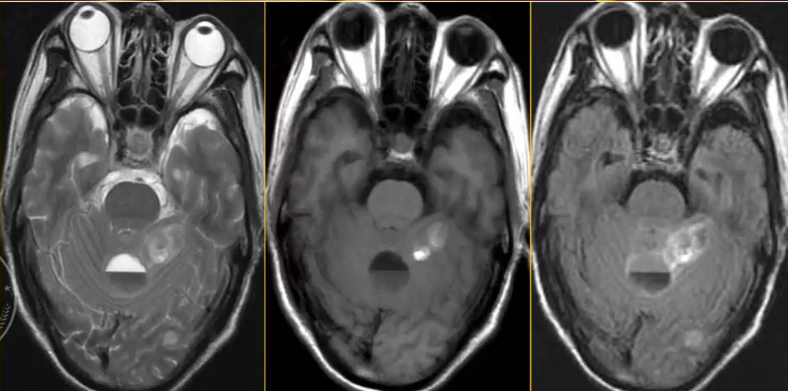

√ 鞍区转移性肿瘤,较少见(1%),鞍上下同时存在,垂体破坏性改变,其它区域常合并转移病灶